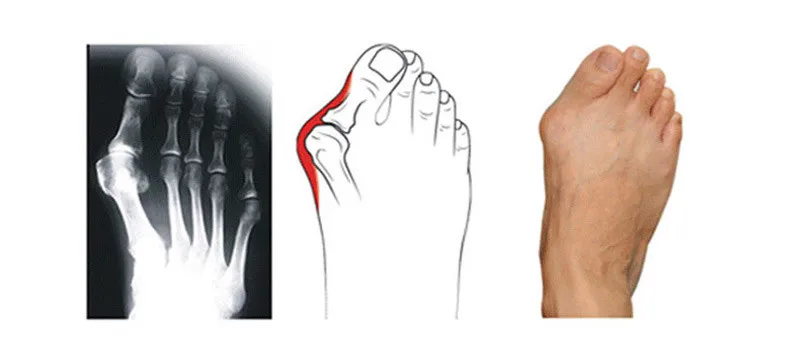

Hallux Valgus, или как принято говорить косточки на ногах (шишки на ногах) — это не только эстетически неблагоприятное изменение в стопе, но и проблема, на которую стоит вовремя обратить внимание, чтобы в дальнейшем избежать хирургического способа лечения и не применять радикальное лечение косточки на ногах. При первой степени и второй, еще возможна коррекция. Во время принятые меры, дадут возможность избежать не желательных и не приятных последствий хирургического вмешательства. Консервативная терапия, назначаемая на начальных стадиях, поможет приостановить усугубление проблемы. Но полная остановка развития возможна лишь в некоторых случаях.

Из-за этой аномалии постепенно деформируются суставы стопы, а именно — в плюсне-фланговом суставе большого пальца формируется и закрепляется подвывих. Внешне это проявляется как выпирание головки кости из-под кожных тканей, внутри происходит медленное обрастание костной тканью плюсневой косточки.

Всего существует четыре стадии деформации стопы при заболевании hallux valgus:

1 степень — почти незаметное смещение пальца (максимум на 20 градусов), которое провоцирует выпячивание шишки. Практически нет болевых ощущений, только огрубление кожи.

2 степень — угол смещения пальца до 30 градусов, появляются боли при долгой ходьбе.

3 степень — смещение до 50 градусов, прогрессирует хрящевой нарост, к острым болям в стопах добавляется припухлость вен и отечность.

4 степень — накладывание пальцев, перекручивание стопы, возникает артроз или бурсит.

Вальгусная деформация. © Gelenk-Klinik

Вальгусная патология первого пальца стопы (искривленность, «шишка» или «косточка») — это довольно распространённое заболевание, прежде всего среди женского населения. вальгусной деформации характерно заметное отклонение большого пальца к наружному краю стопы, что может спровоцировать искривление остальных пальцев. Все это создает довольно неэстетичную картину.

При вальгусном отклонении плюснефаланговый сустав искривляется и склоняется к наружной стороне стопы. Во время Hallux valgus на 1-ом плюснефаланговом суставе выпирает отечная и воспаленная головка плюсневой кости, которая не дает человеку носить красивую обувь.

Почти всегда специалисты, предлагающие ортопедическое лечение стопы в Германии, связывают это заболевание с поперечным плоскостопием или со слабым связочным аппаратом. По началу нарушается баланс функции связок, сухожилий и мышц, после чего изменяется структура костей и суставов.

После того как ослабли некоторые элементы, которые образуют форму стопы, проявляется поперечное плоскостопие, а так же наблюдается увеличение угла отклонения 1-ого пальца и появление той самой «шишки». Поэтому на 1-ом плюснефаланговом суставе все больше проявляется болезненный, и воспаленный выступ кости,являющийся основным признаком Hallux valgus.